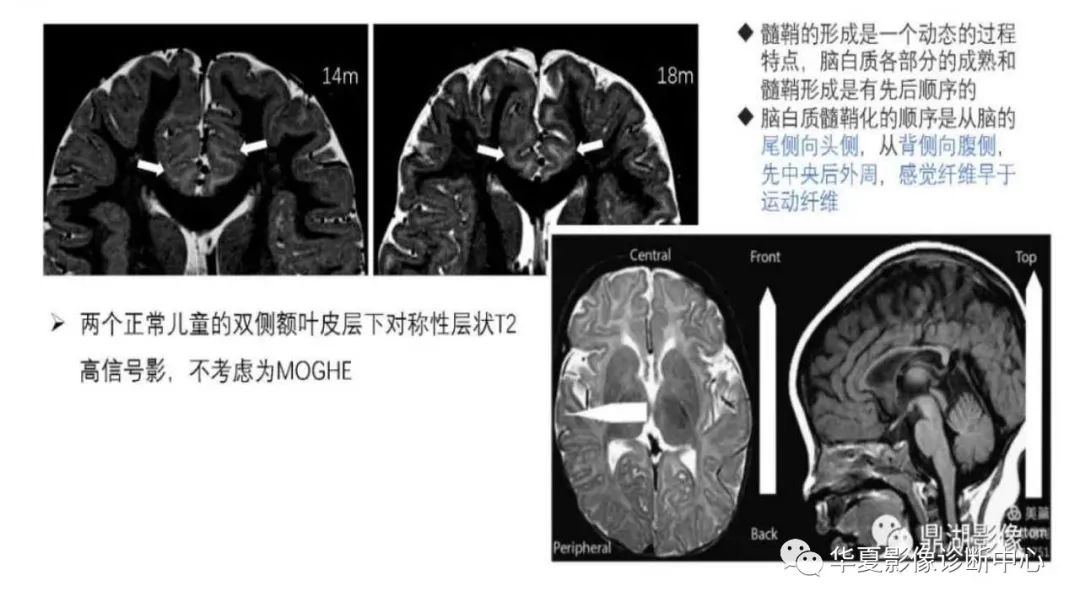

MOGHE的MRI诊断与鉴别诊断-2